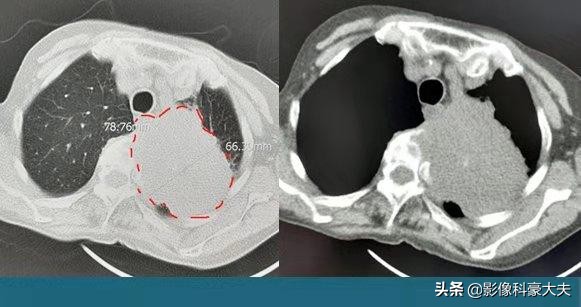

这位老人是中心型肺癌,因为发现比较早,癌细胞局限在做肺下叶支气管,做的左肺下叶完整切除,目前5年多了没有复发。有些中心型肺癌侵犯肺门重要结构,需要扩大切除,比如做一侧肺全切。还有些无法切除,就只能保守治疗了。

像这位病人,是因为股骨干骨折出院前体检发现的肺癌。这种因为其他疾病而发现肺癌的情况很常见,肺癌的发病率实在太高,要重视体检筛查!